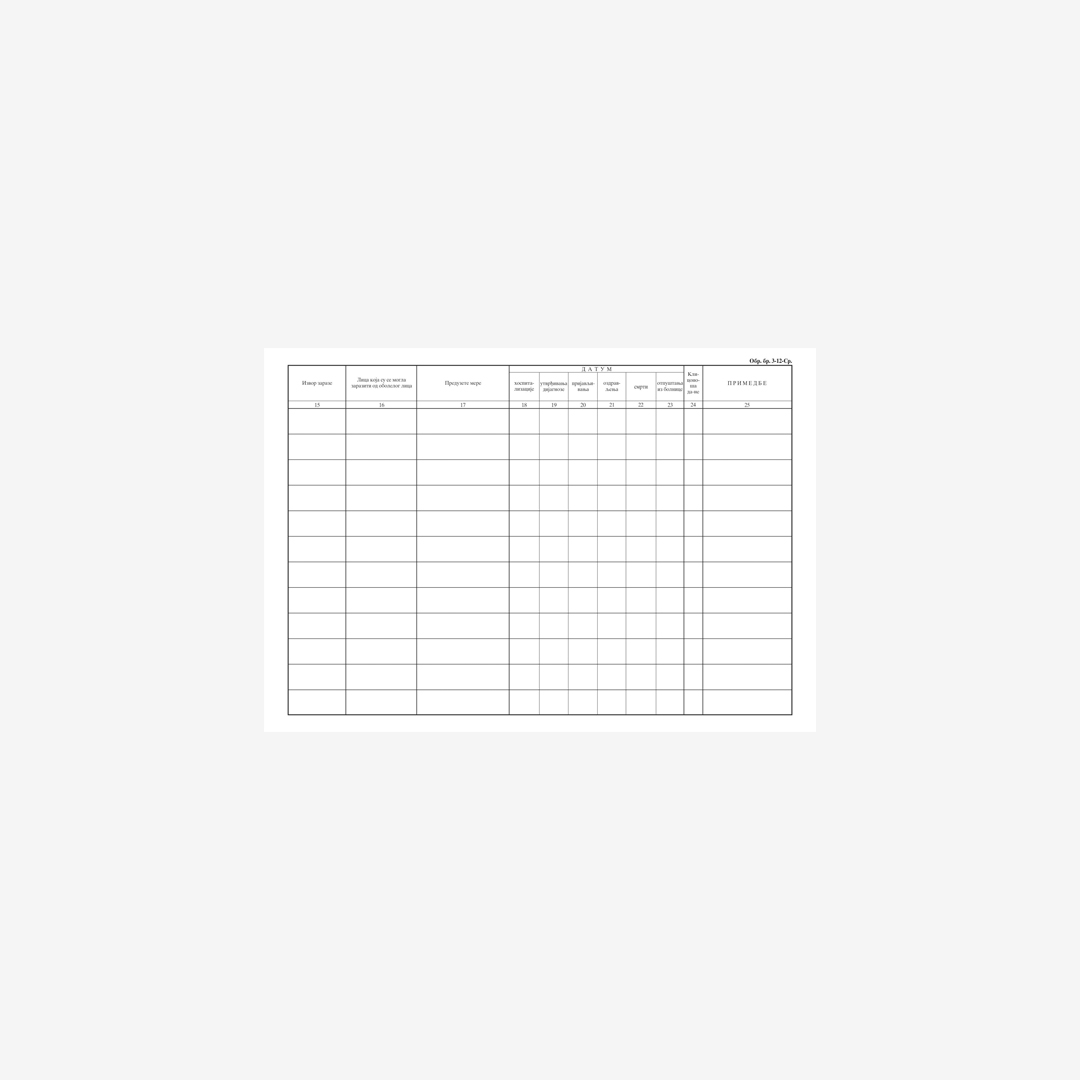

- Knjiga evidencija zaraznih bolesti tvrd povez, B4, 100 lista.